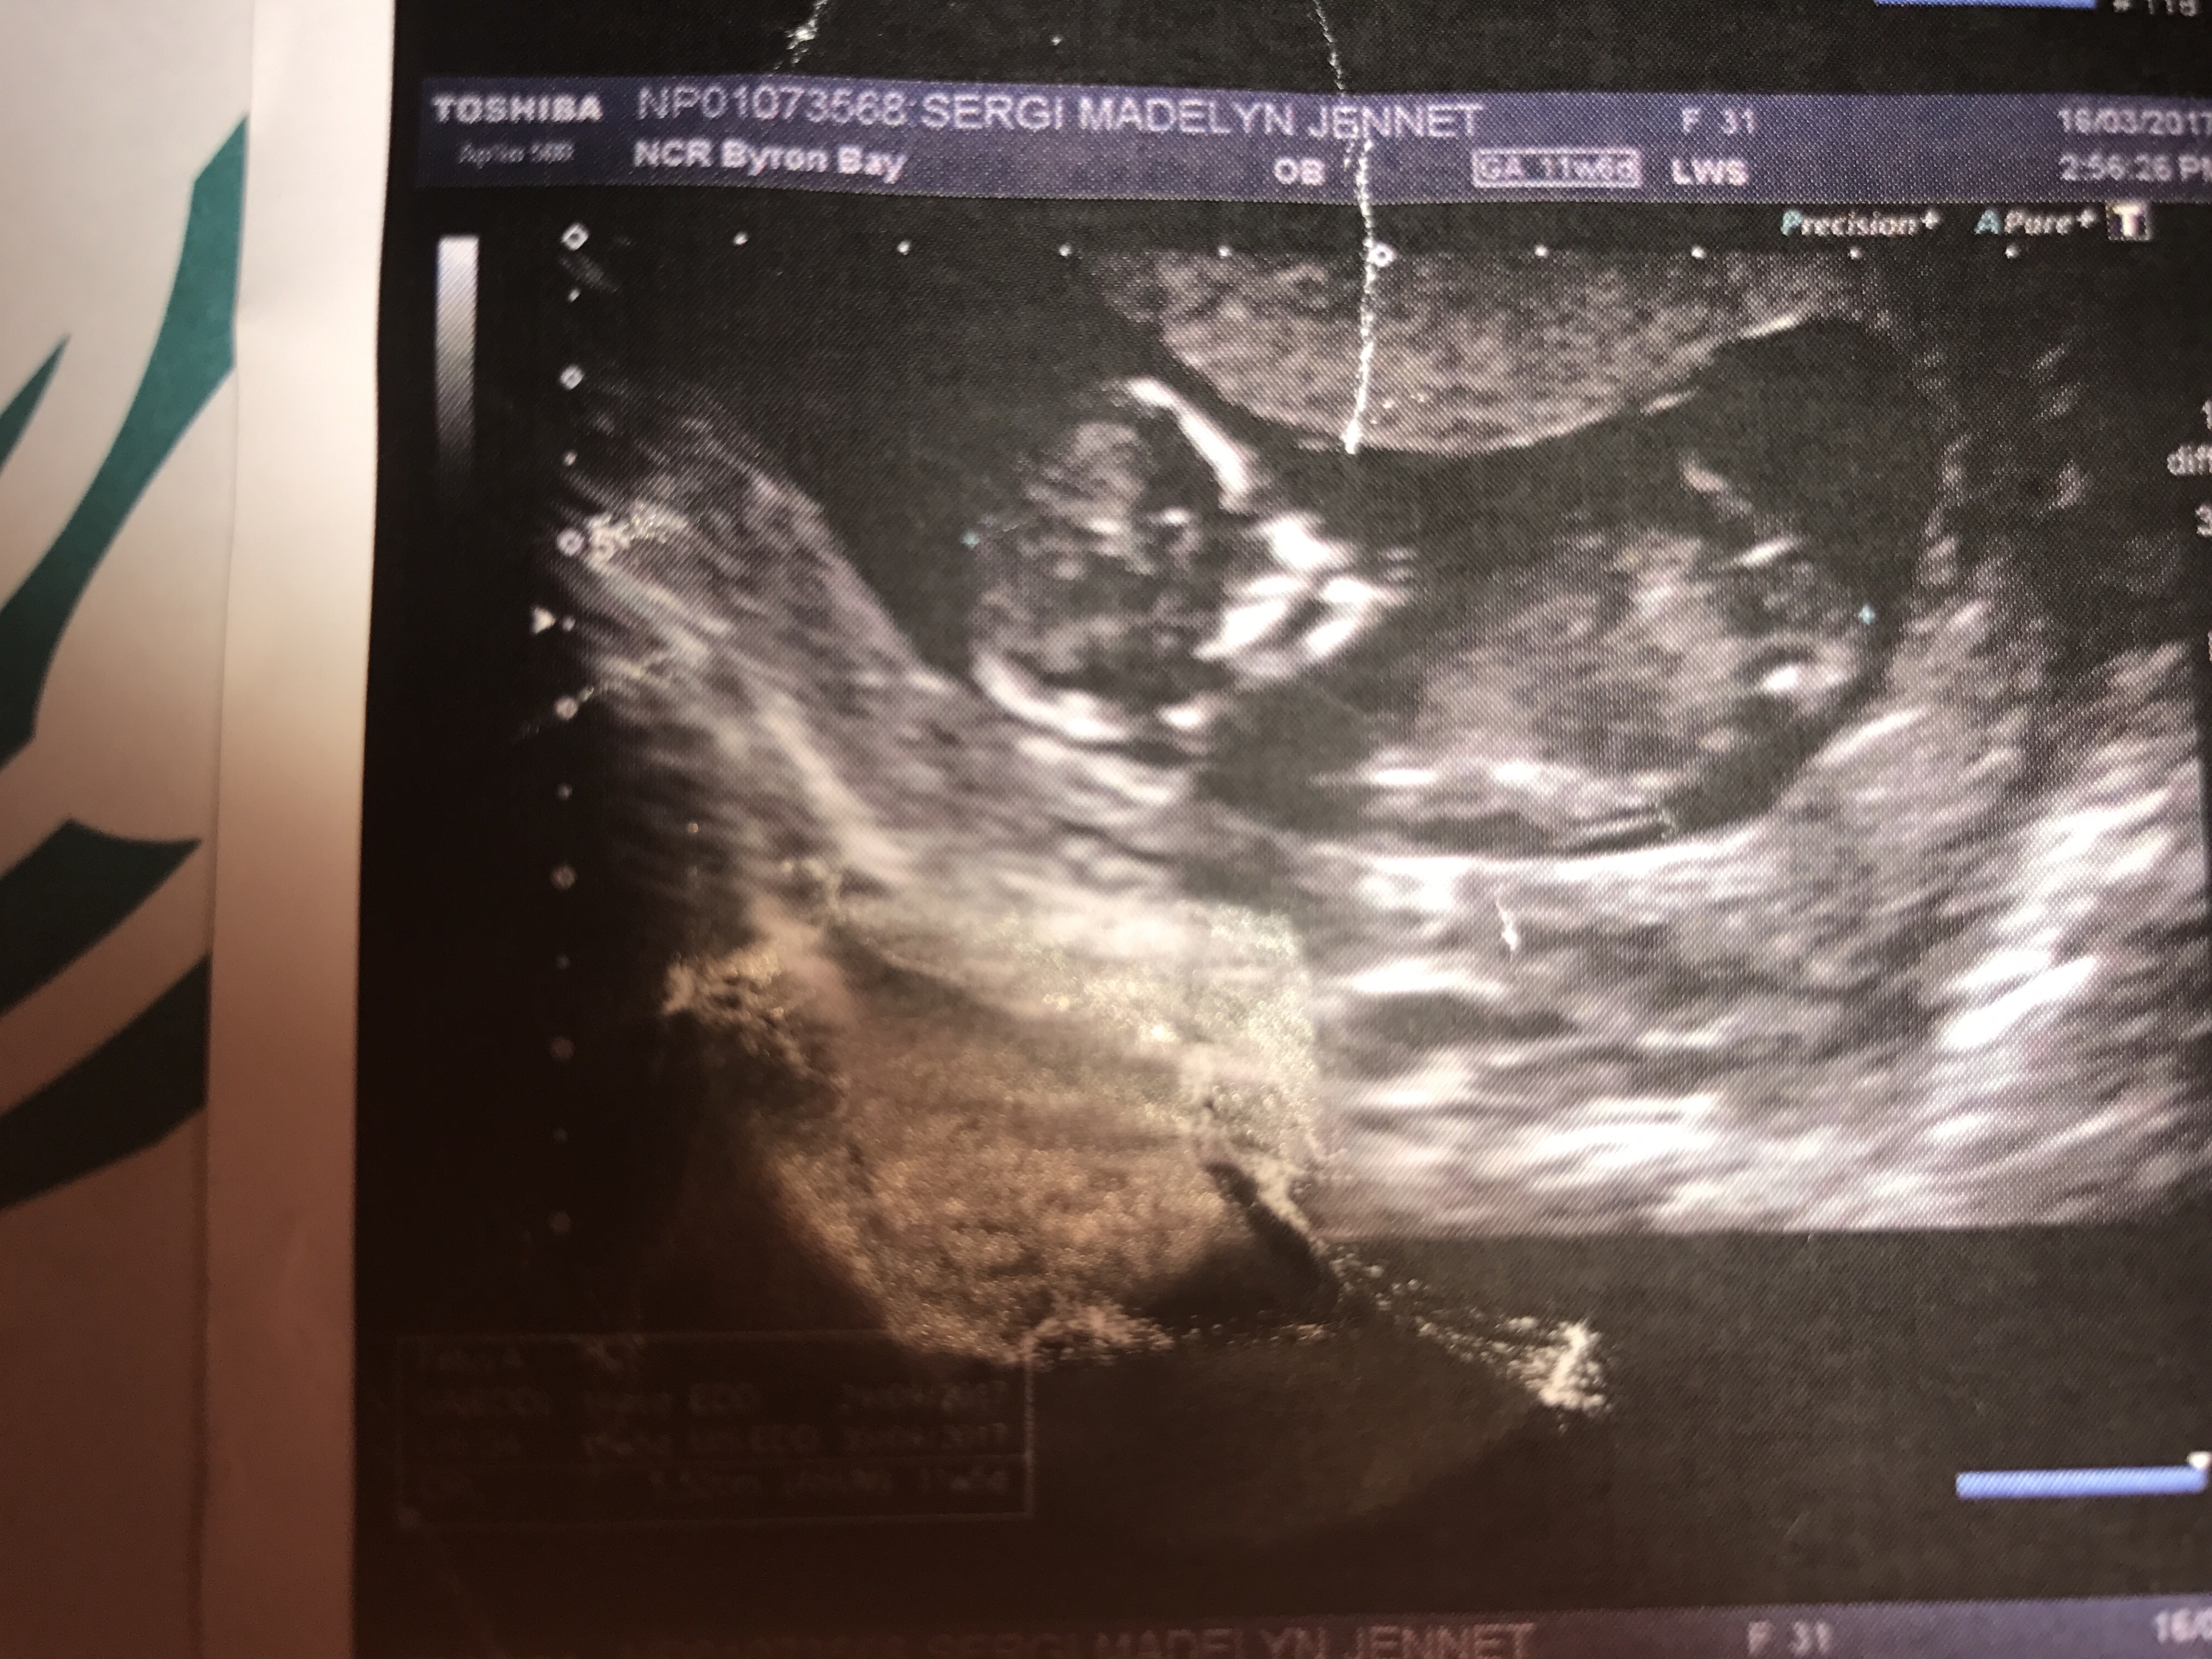

I am desperately trying to find out from my ultrasound if I'm having a boy or a girl! I have been told a girl but also that the pic is not clear enough! I can see the nub and it appears horizontal but I am no expert! I would just love anyone to take a guess PLEASE!!